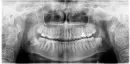

4 года назад проходила ортодонтическое лечение, есть опасения, что зубы поедут. Насторожила ситуация с нижней лежащей восьмеркой. Ощущение, что она травмирует соседнюю семерку.

Если возможно оценить состояние зубов на снимке:

Я бы порекомендовала начать удаление с ретинированных нижних 8-х зубов, т.к. для них места в зубном ряду явно не хватает, это видно по снимку, в то время, как для верхних место есть и они прорезались, тем самым всё, что могли изменить, они уже сделали.

Выбирая между нижними 8-ми, я бы порекомендовала начать с правой (лежащей).